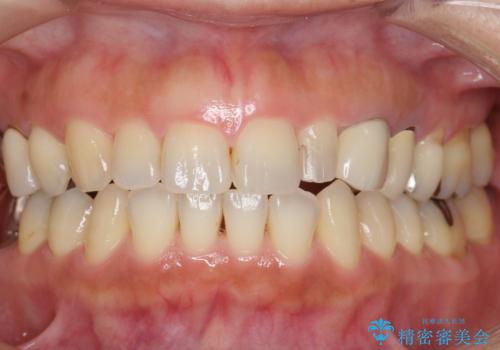

前歯が左右対称じゃない 保険の被せ物をきれいにしたい ホワイトニング併用

左右対称に仕上げることができ、治療には非常に満足していただきました。